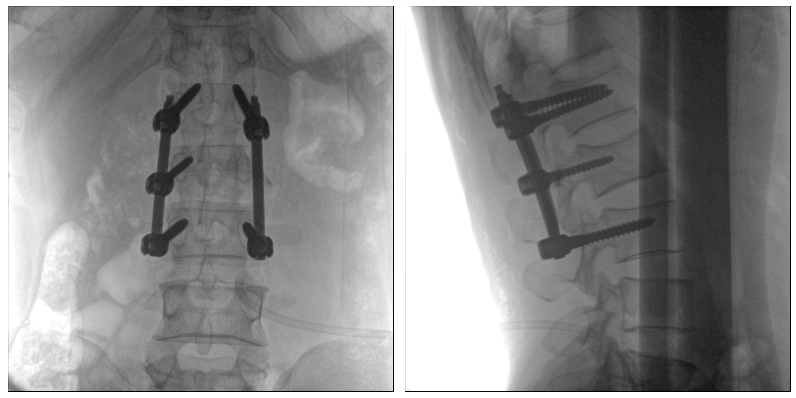

從下圖中可以看到二維影像能夠提供目標(biāo)區(qū)域在某一個平面的重疊影像,雖然因為人體不同組織的密度差異,使得圖像具有較為豐富的信息量,但組織間的相互重疊還是會出現(xiàn),諸如空間位置等眾多信息在影像中遺失或不可辨認(rèn)的情況,影響了醫(yī)生對信息的收集與應(yīng)用。

術(shù)中二維影像